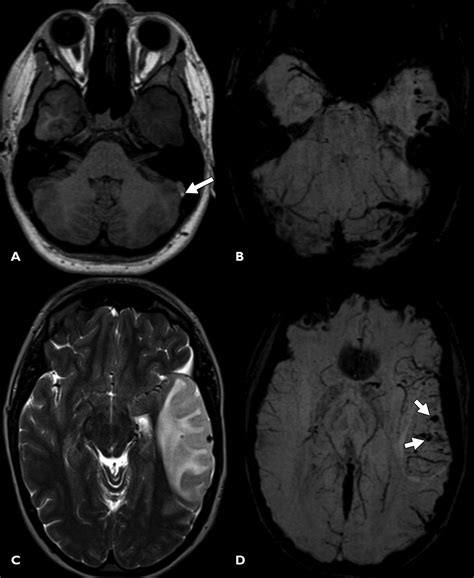

• Traumatic Brain Injury (TBI): SWI is highly sensitive to the detection of Diffuse Axonal Injury (DAI) and microhemorrhages resulting from shear forces during trauma.

• Cerebrovascular Disease: It allows for the identification of venous thrombosis, cavernous malformations, and the assessment of vascular reserve.

• Brain Tumors: SWI helps differentiate between tumor types by assessing the degree of intratumoral hemorrhage and the organization of the microvasculature.

Radiologists look for "blooming effects" on the images, where small, dark spots represent paramagnetic substances like blood products. Because the signal decay is accelerated in regions with high iron or deoxyhemoglobin content, these areas appear as dark, high-contrast signals. Interpreting these images requires an understanding of how to differentiate between normal venous blood and pathological hemorrhages. For instance, the presence of blood in deep brain nuclei versus the cortex can indicate vastly different underlying etiologies, such as hypertensive vasculopathy or cerebral amyloid angiopathy.